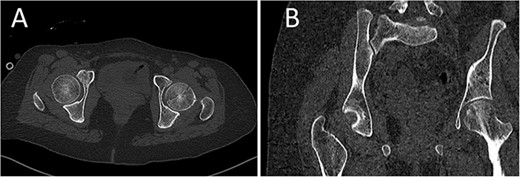

A medically free 42-year female presented to our institute as a life-saving case from a different hospital as she was a victim of unrestrained road traffic accident 2 days prior to presentation. Upon assessment in the emergency department (ER), she was conscious and oriented, and was found to have bilateral lung contusion, and multiple fractures of ribs. She also had a left sided vertical femoral head fracture dislocation comprising around 40% of the femoral head (Fig. 1). Closed reduction under conscious sedation was done in the ER, which was successful based on post-reduction imaging studies (Fig. 2). Her chest injuries were treated with chest tube and observation for 10 days. During that time, discussion was made with the patient regarding her situation and conservative management was chosen by way of bed rest and continuation of skeletal traction for 4 weeks with serial radiographs in the hospital on a weekly basis after clearance of her chest injuries. Skeletal traction was discontinued and she was advised to continue bed to wheelchair mobilization for an additional 2 weeks. After 6-weeks from the injury, a Computed Tomography (CT) was done to the patient and revealed signs of fracture healing (Fig. 3). At 3-years after the injury, she was found to have full painless range of motion of the affected hip and has resumed her activity of daily living without any complaints and the images showed a symmetrical joint space of the hips (Fig. 4).

CT scan of the pelvis showing axial (A) and coronal (B) cuts at 6-week post-injury showing signs of healing of the left fractured femoral head with a concentric hip joint.